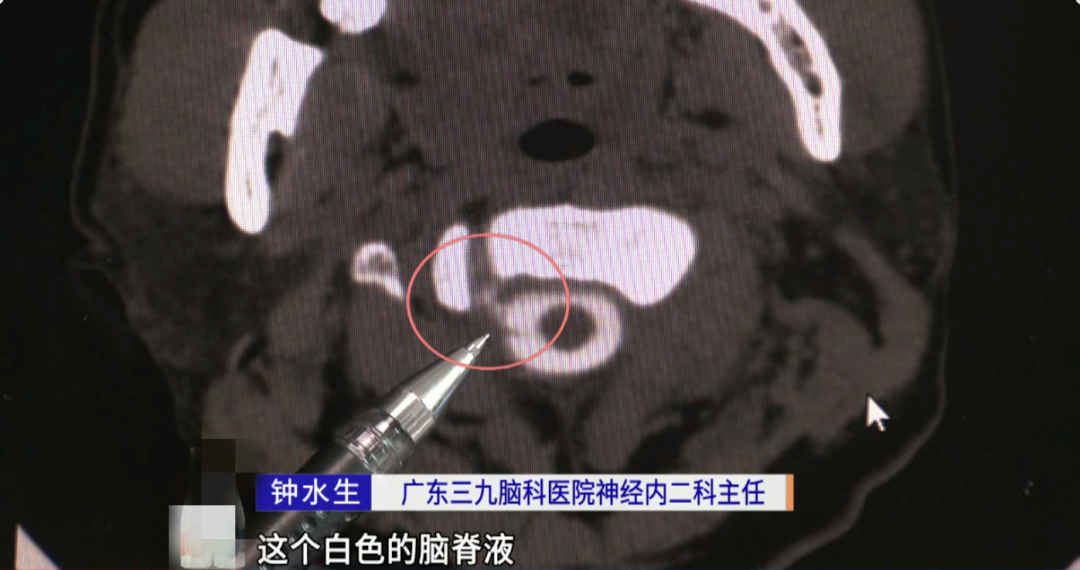

据了解,阿维曾在广东珠海的医院求医,医生说他是颈椎问题,但经过治疗都没效果。于是,他来到了广东三九脑科医院,经诊断,阿维之所以头痛是因为脑“漏水”,也就是脑脊液发生了渗漏。

广东三九脑科医院神经内二科主任钟水生解释,“可能有骨刺把他的硬脊膜刺破了,出现了脑脊液的渗漏。”

脑子里的“水”在医学上叫脑脊液,是无色的透明液体,人体每天都会产生一定量的脑脊液,其作用是为脑细胞提供营养,并运走脑组织的代谢产物,起到缓冲大脑和脊髓压力的作用。一般情况下,脑脊液是在颅内产生和循环,与外界不相通。

而脑脊液被硬膜囊包围,一旦硬膜囊破了,脑脊液逐渐漏出,脑组织就失去了浮力支撑,会跟神经形成拉力,使人出现头痛、恶心、耳鸣等症状。如不尽早处理,容易引起颅内出血、脑疝,甚至威胁生命。